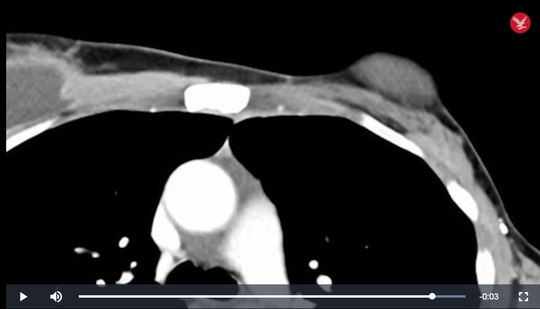

Khối u rất lớn trong ngực bà Perkins thể hiện trên phim MRI

- ảnh cắt từ clip của NCI

Kết quả là hệ miễn dịch của bà Perkins đã phá hủy rất nhanh chóng khối u chính lẫn các điểm di căn và tự làm bà khỏi bệnh. Hiện nay, sau 2 năm, các bác sĩ đã kiểm tra lại nhiều lần và không phát hiện bất kỳ dấu hiệu nào khác của bệnh ung thư trong cơ thể bà.

Ngực bà Perkins sau điều trị: khối u hoàn toàn biến mất